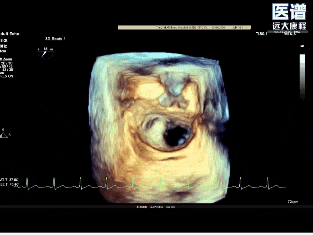

TEE

TEE-3D

病变位置为:A1邻近交界处脱垂;宽度/高度:1.08cm/0.29cm;A1/P1瓣叶长度:1.38cm/1.17cm;前后径(AP直径):3.56cm;二尖瓣口面积:4.39cm2

重度DMR,LVEF 61%,LVIDd 5.62cm,LVIDs 3.27cm,VCW 0.72cm,EROA=0.47cm2;RV=83ml,PG mean 3mmHg,PASP 51mmHg。